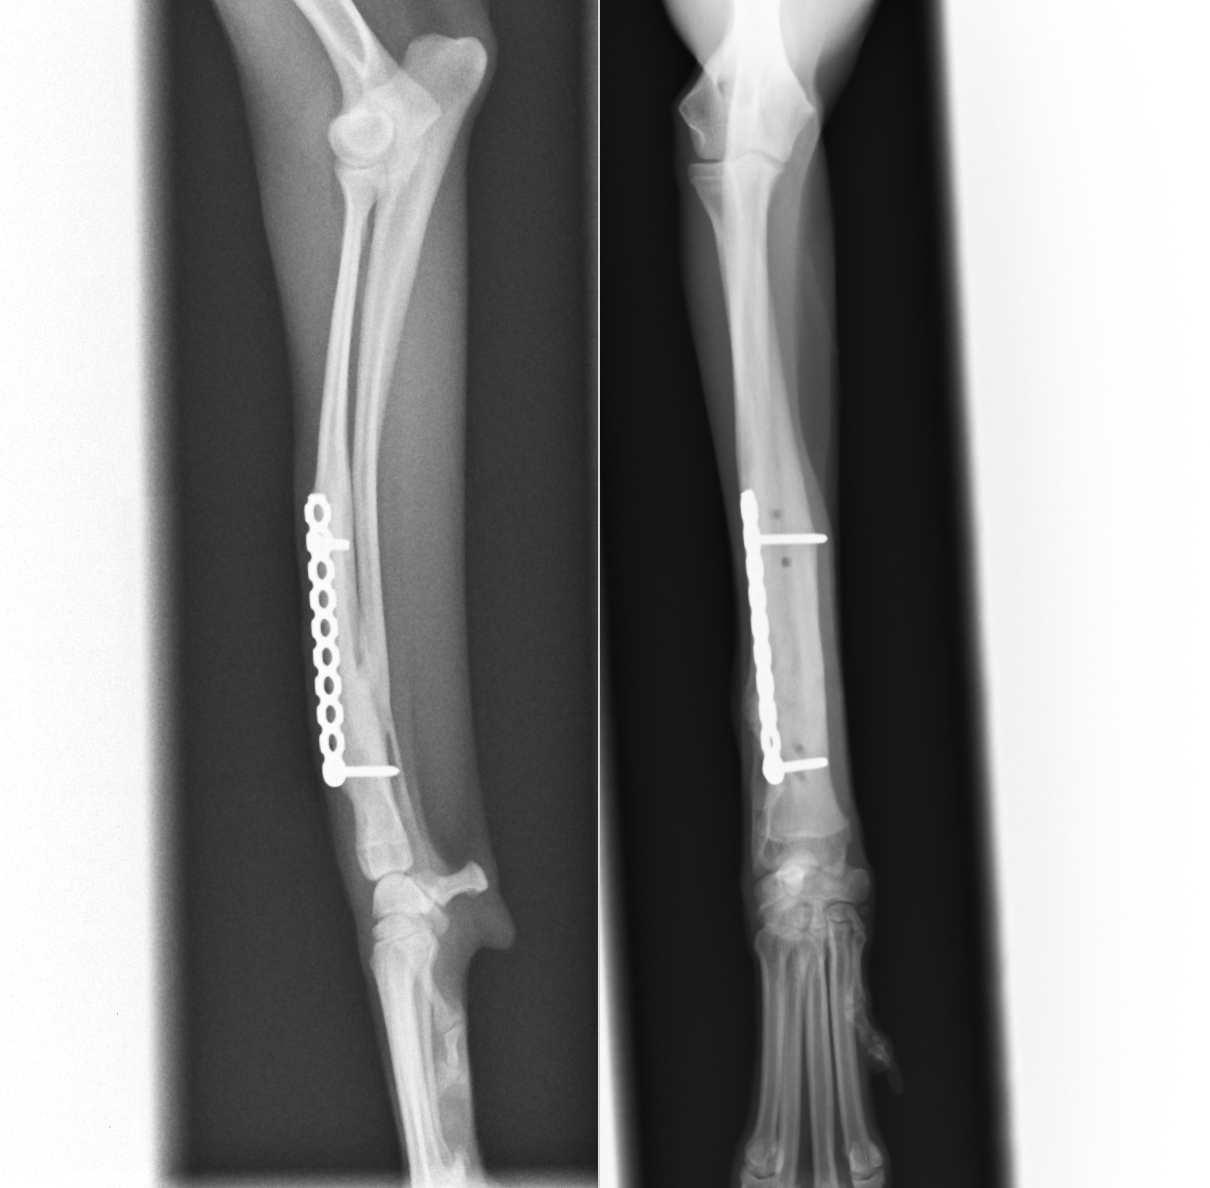

骨折端からの距離に余裕がある場合には真っ直ぐなプレートを設置します。

正面のプレートを取ったところです。骨折部位はきれいに癒合しており、尺骨も癒合しているのがわかります。このようにいっぺんにすべてのプレートを取るのではなく順序立てて取ることで(ディスタビライゼーションといいます)、スクリューが入っていたところでの骨折を予防することができます。